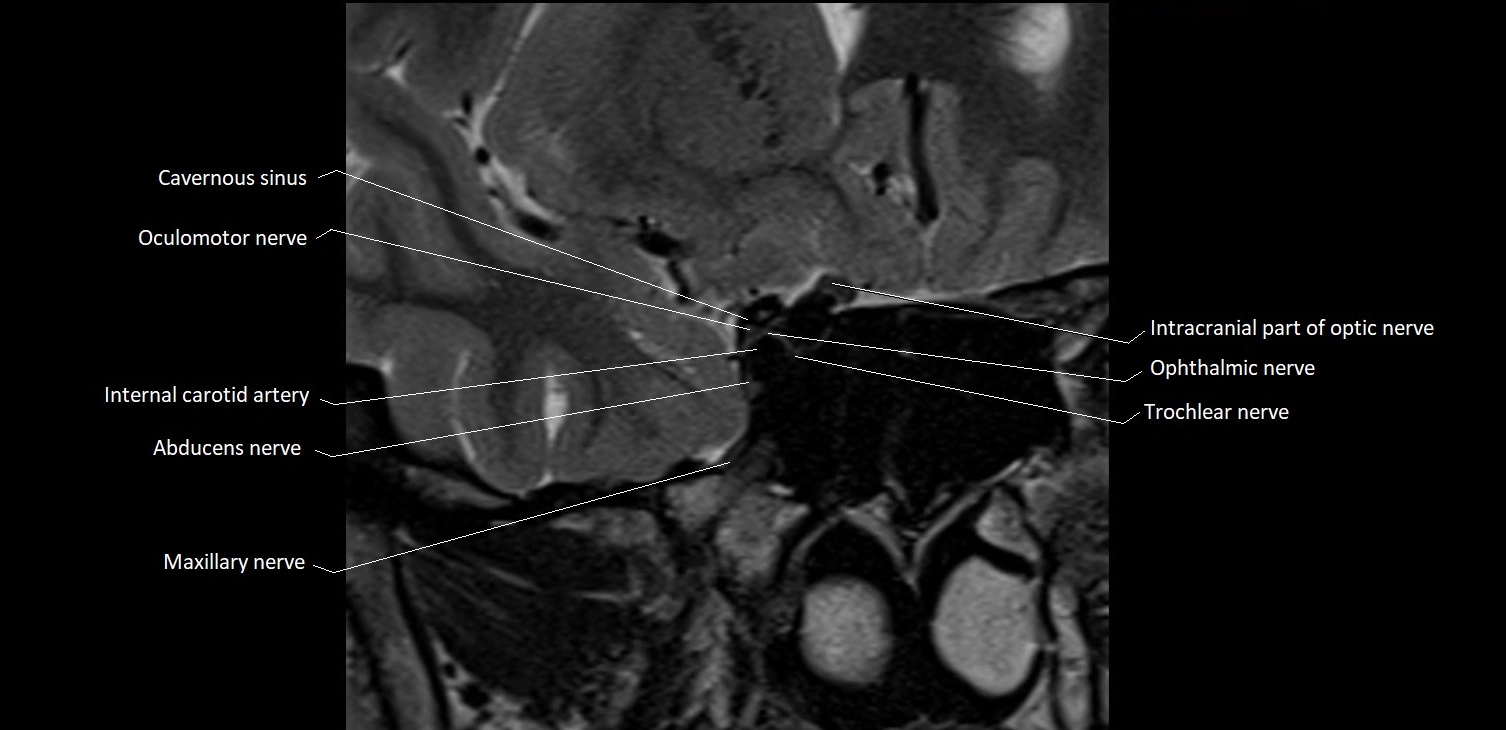

- Abducens nerve (Cranial nerve VI)

- Oculomotor Nerve (Cranial Nerve III)

- Maxillary nerve

- Trochlear nerve (Cranial nerve IV)

- Intracranial part of optic nerve

- Optic Nerve (Cranial Nerve II)